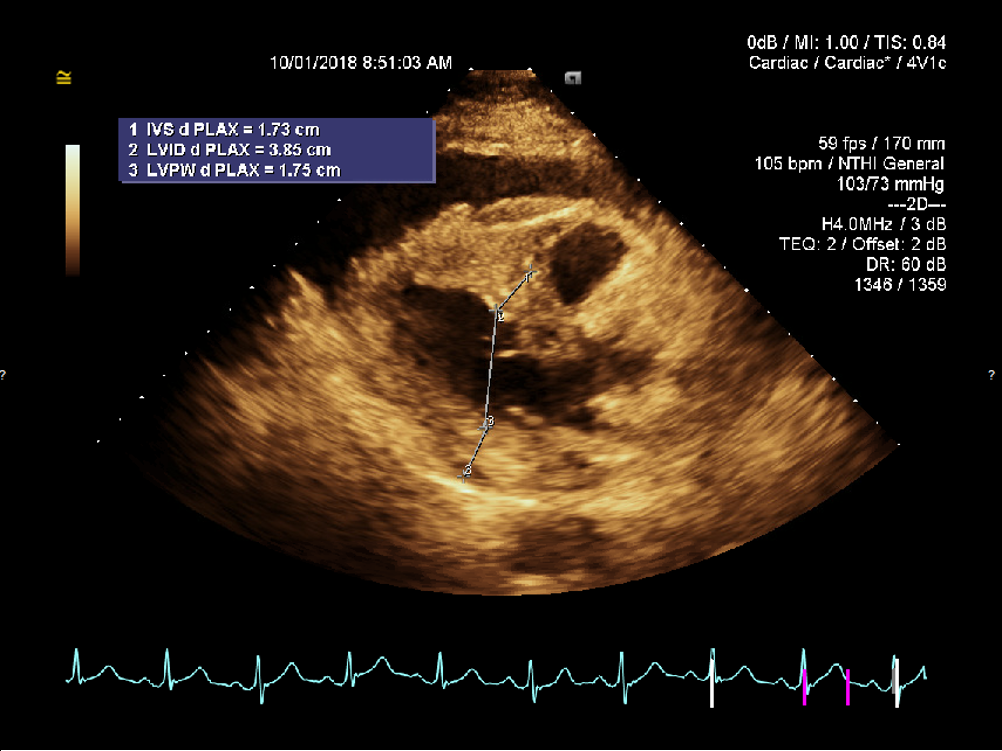

A preliminary bedside diagnosis of cardiac tamponade was made and was confirmed by urgent echocardiography, the results of which showed a large, hemodynamically significant pericardial effusion with right ventricular diastolic collapse (Figure 4).

Figure 4. Echocardiography showing a large pericardial effusion.

Collapse of the right atrium at end diastole and the right ventricle in early diastole are hallmark findings on echocardiography and reflect intrapericardial pressure exceeding intracardiac pressure during diastole.3 Echocardiography is an extremely important diagnostic tool, since it can detect pericardial effusion even before overt tamponade.7 Our patient had evidence of right ventricular diastolic collapse (Figure 3), which is a less sensitive but more specific finding of tamponade.